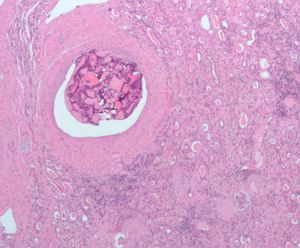

복강 내 이물질은 결국 이물 육아종에 갇히게 된다. 매우 드문 경우로, 잔류 자궁외 임신의 경우 석태아가 형성되기도 하는데, 이는 태아가 너무 커서 재흡수될 수 없고 감염으로부터 주변 조직을 보호하기 위해 석회화되는 것이다.[13]